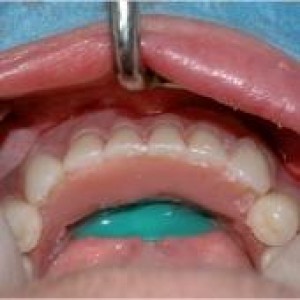

Obiettivi. Lo scopo di questo articolo è descrivere una serie di tecniche utili a migliorare l'estetica delle riabilitazioni implantari nel mascellare anteriore.Materiali e metodi. Si descrive...